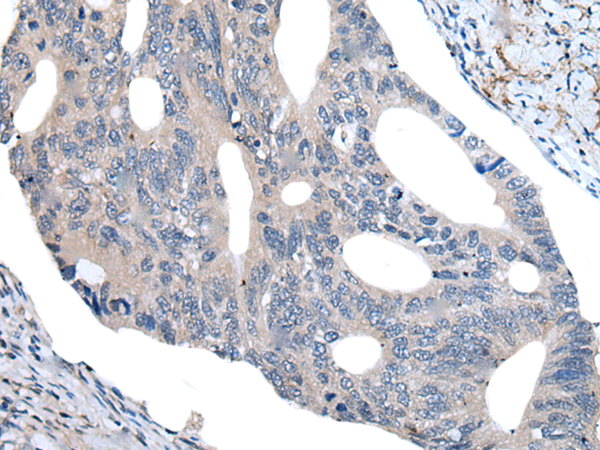

IHC positive control:

Human colorectal cancer and human tonsil

IHC Recommend dilution:

40-200